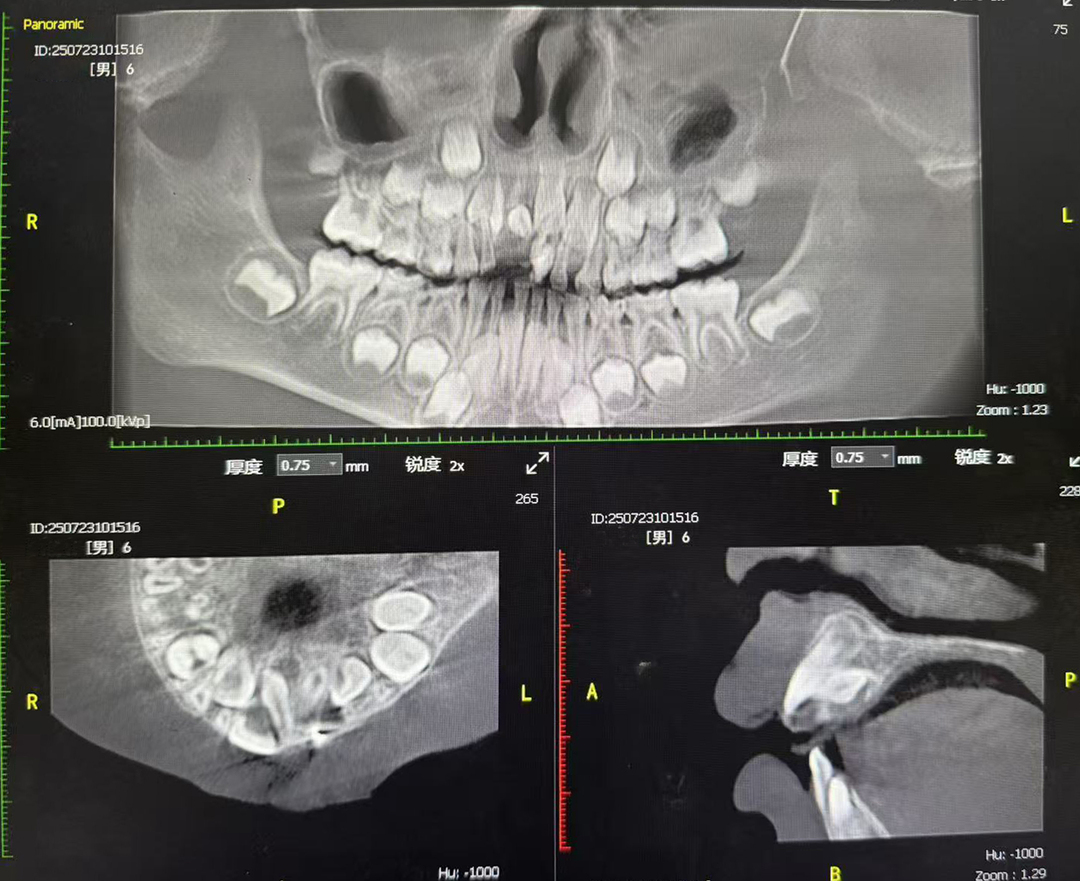

手术当天上午,在麻醉科团队的密切配合下,陈志华副主任医师亲自主刀。术中,精准定位多生牙位置,小心翼翼地分离周围组织,避开恒牙胚及重要神经血管,同时实时监测患儿生命体征。经过精心操作,成功拔除2颗埋伏多生牙。术后,患儿在ICU苏醒顺利,无明显不适,患儿于下午1点左右顺利出院。

术后口腔CT检查